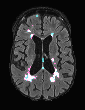

In recent years, data-driven machine learning (ML) methods have revolutionized the computer vision community by providing novel efficient solutions to many unsolved (medical) image analysis problems. However, due to the increasing privacy concerns and data fragmentation on many different sites, existing medical data are not fully utilized, thus limiting the potential of ML. Federated learning (FL) enables multiple parties to collaboratively train a ML model without exchanging local data. However, data heterogeneity (non-IID) among the distributed clients is yet a challenge. To this end, we propose a novel federated method, denoted Federated Disentanglement (FedDis), to disentangle the parameter space into shape and appearance, and only share the shape parameter with the clients. FedDis is based on the assumption that the anatomical structure in brain MRI images is similar across multiple institutions, and sharing the shape knowledge would be beneficial in anomaly detection. In this paper, we leverage healthy brain scans of 623 subjects from multiple sites with real data (OASIS, ADNI) in a privacy-preserving fashion to learn a model of normal anatomy, that allows to segment abnormal structures. We demonstrate a superior performance of FedDis on real pathological databases containing 109 subjects; two publicly available MS Lesions (MSLUB, MSISBI), and an in-house database with MS and Glioblastoma (MSI and GBI). FedDis achieved an average dice performance of 0.38, outperforming the state-of-the-art (SOTA) auto-encoder by 42% and the SOTA federated method by 11%. Further, we illustrate that FedDis learns a shape embedding that is orthogonal to the appearance and consistent under different intensity augmentations.